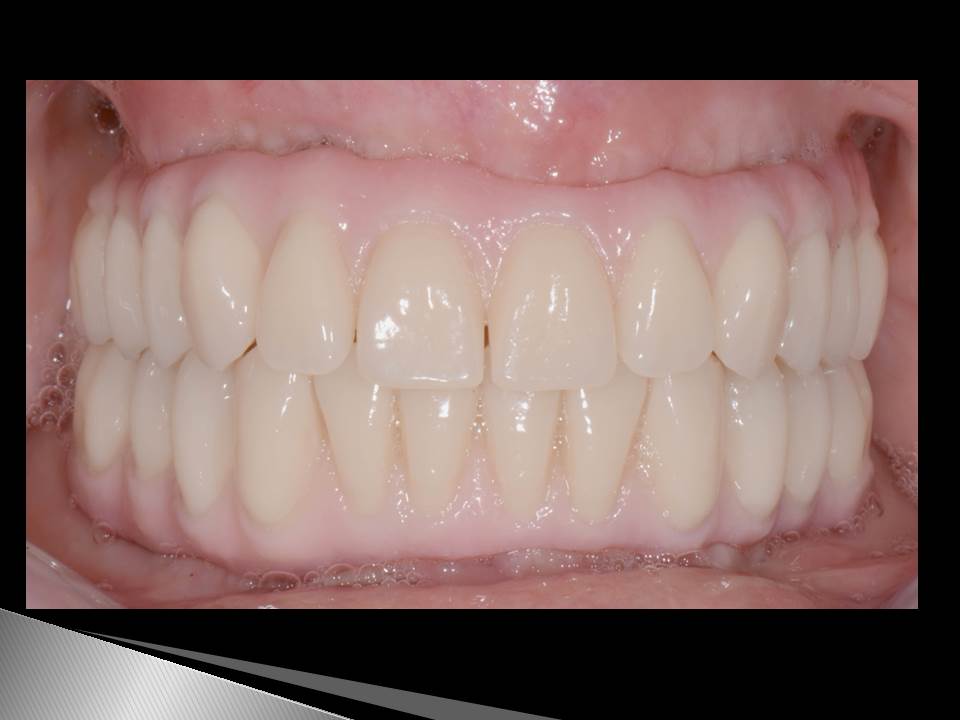

Prótesis fija OT BRIDGE

OT Equator Biologic Abutment